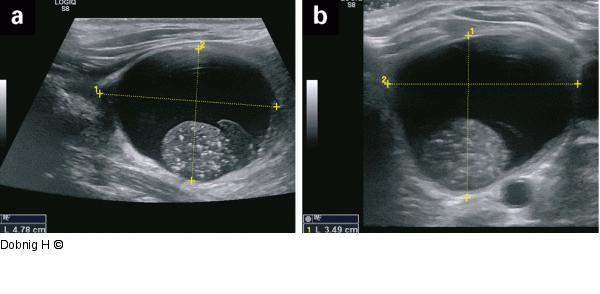

Abbildung 11a-b: Alkoholablation - Schilddrüse Längsschnitt (a) und Horizontalschnitt (b) durch eine 3,5 × 4,0 × 4,8 cm große Zyste mit lokaler Drucksymptomatik. Zystenvolumen 31 ml; auswärts bereits zweimal punktiert. In einem ersten Schritt wurde eine gezielte FNP des kugeligen Knotenparenchyms durchgeführt (benigne Zytologie). |

Längsschnitt (a) und Horizontalschnitt (b) durch eine 3,5 × 4,0 × 4,8 cm große Zyste mit lokaler Drucksymptomatik. Zystenvolumen 31 ml; auswärts bereits zweimal punktiert. In einem ersten Schritt wurde eine gezielte FNP des kugeligen Knotenparenchyms durchgeführt (benigne Zytologie). |